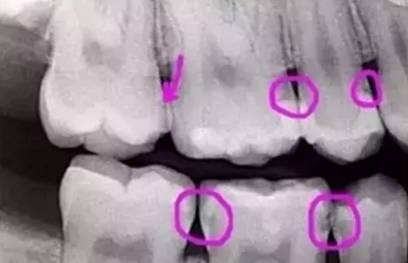

圈出嚟嘅地方或多或少都有啲蛀牙,不過啲蛀牙唔係全部都見得到。呢啲蛀牙都仲係好淺,最多食野嗰陣卡住啲牙齒,個牙齒仲有啲對冷水敏感。

暗啲位講明龍齒巳經攰咗好勁啦!